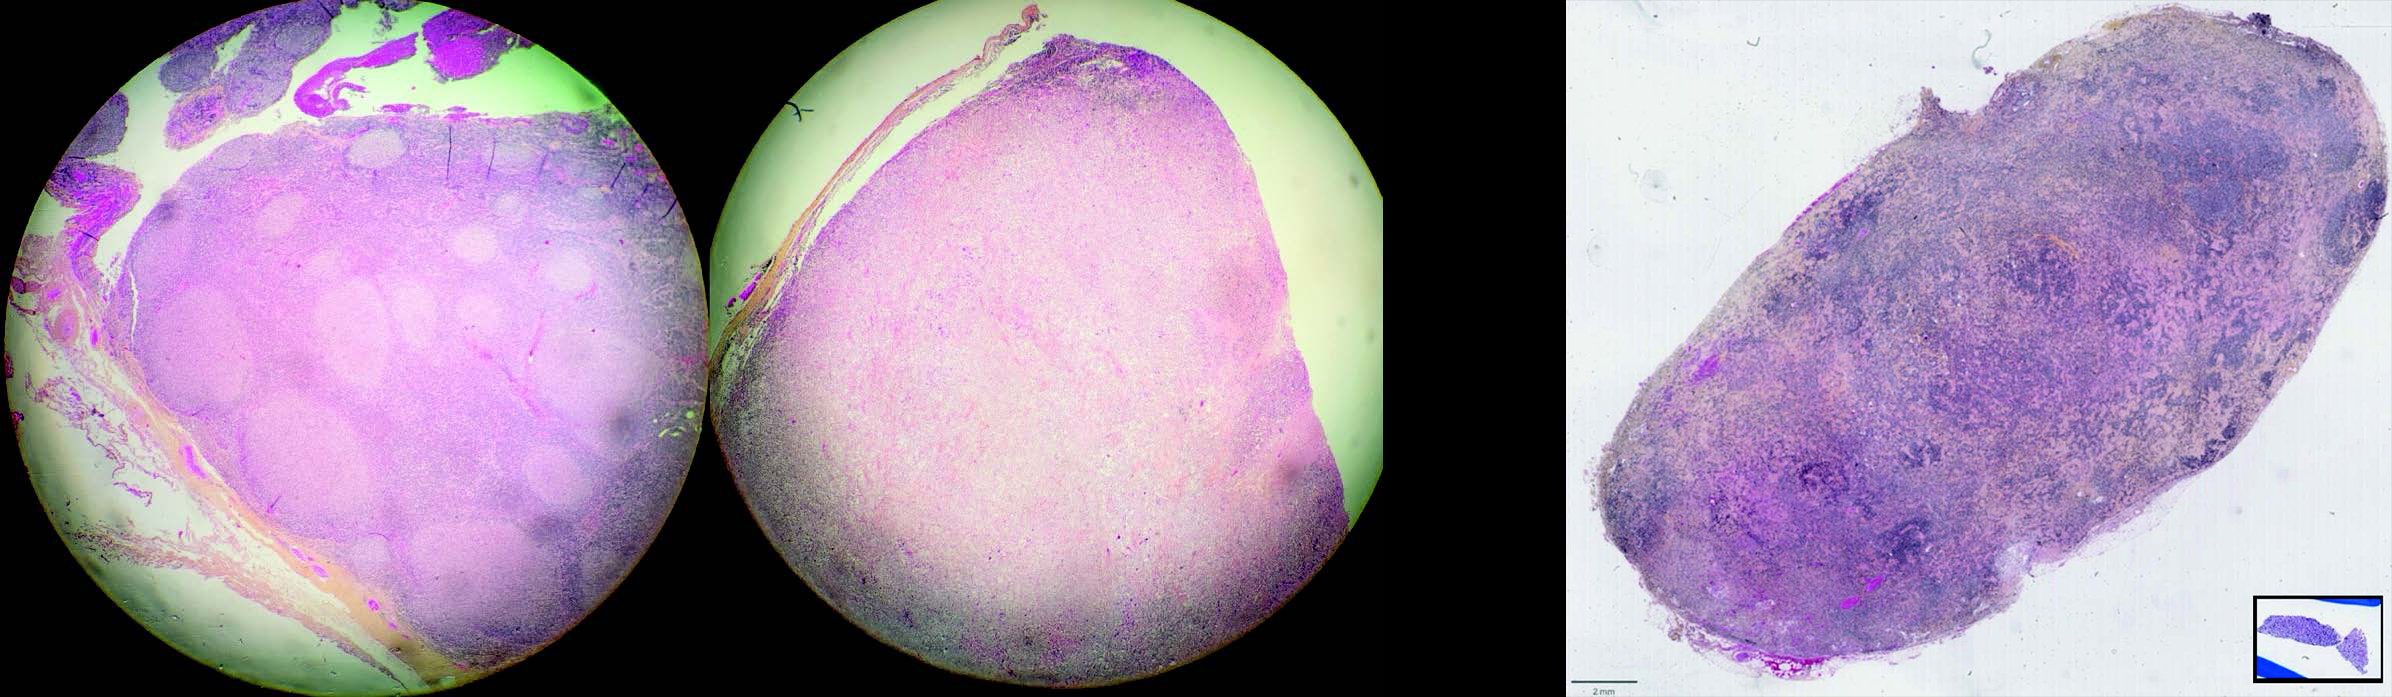

De plus, la taille du prélèvement revêt une importance capitale : il est fréquent qu'un diagnostic soit incertain, voire impossible en raison d'un prélèvement de petite taille (Figure 2).

Une exérèse ganglionnaire sera toujours préférable à une biopsie, de façon encore plus marquée de nos jours, où le manque de matériel peut limiter la réalisation de techniques de pointe.

Figure 1 HES – Prélèvement du ganglion le plus hypermétabolique. Patient présentant une polyadénopathie. L'exérèse de deux ganglions cervicaux a montré un lymphome folliculaire dans l'un (gauche), et transformé en lymphome diffus dans l'autre (droite).

Figure 2 HPS – Taille prélèvement - Exérèse ganglionnaire (gauche) et microbiopsie ganglionnaire (encadré noir) à échelle équivalente